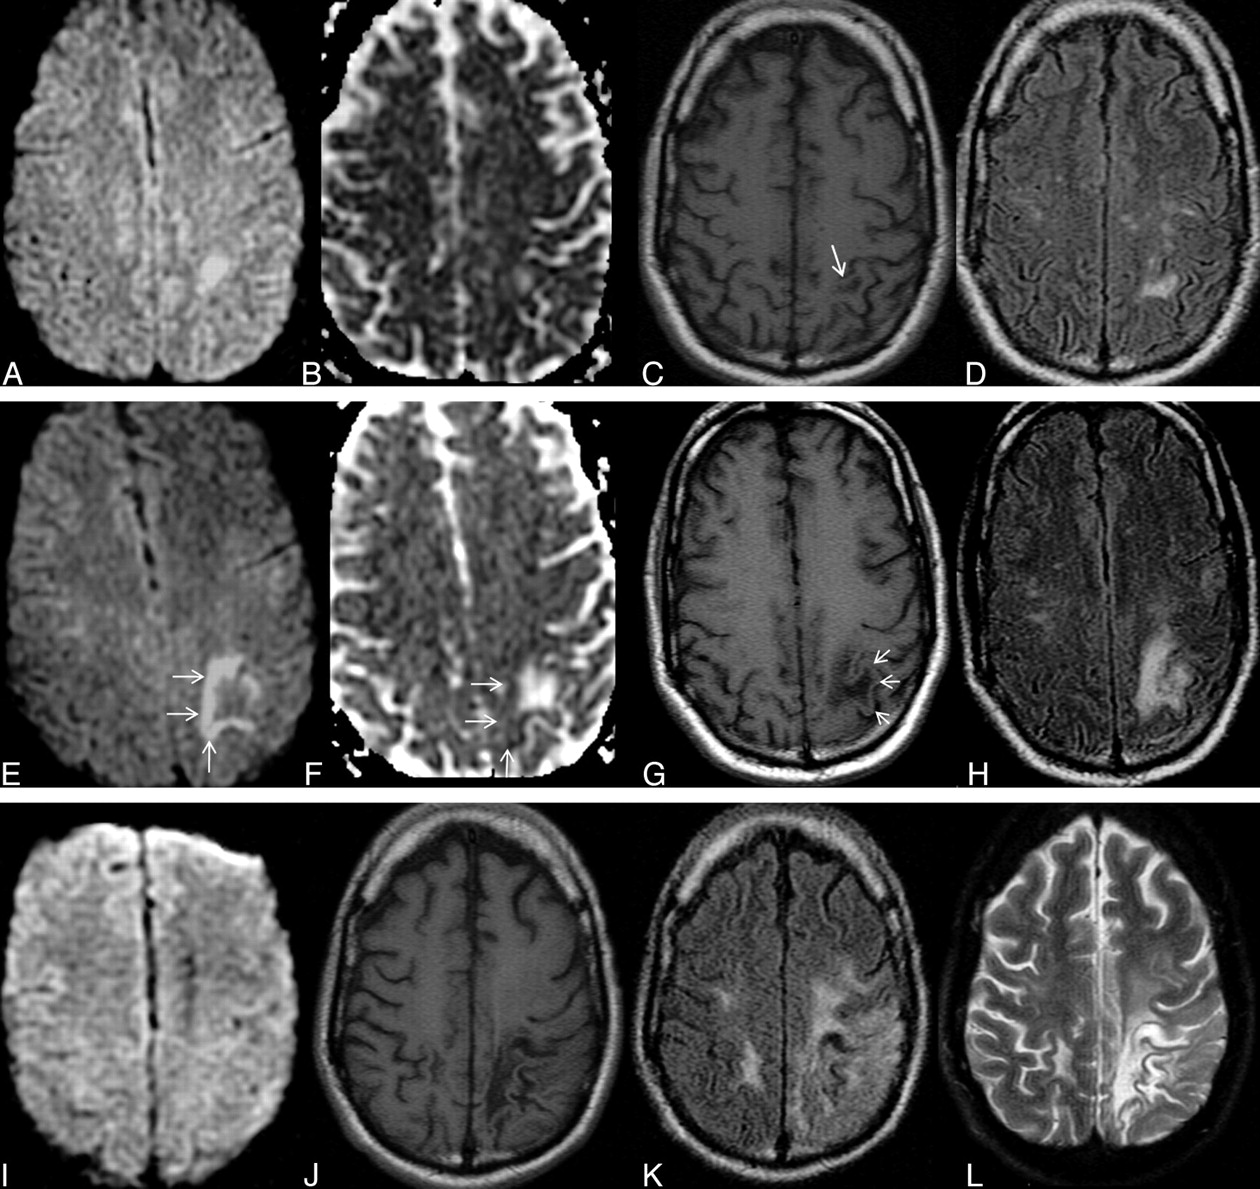

Typical supratentorial right frontal cPML in an HIV-positive patient. A, On DWI, the lesion shows typical restricted diffusion along the advancing edge posteriorly (arrows) and facilitated diffusion centrally. B, On the ADC map, ADC value is low at the posterior advancing edge (arrow) and high at the center of the lesion. C, The lesion typically involves the subcortical U-fiber and is hypointense (relative to gray matter) on the T1-weighted sequence. Note the absence of mass effect from this moderate-sized lesion. D, There is no enhancement of the lesion on the postcontrast T1-weighted sequence. E, On the FLAIR sequence, there is hyperintensity in most parts of the lesion. Note the inversion of the FLAIR high signal anteriorly (arrow) due to intralesional cystic change. F, On the T2-weighted sequence, the entire lesion is hyperintense. Note the adjacent anterior cortex is relatively spared (arrow). G, On perfusion imaging, cerebral blood volume of the lesion is lower (arrow) than that of the contralateral white matter.

Typical disease course of cPML in an HIV-positive patient receiving HAART. Top panel, a set of images at presentation with focal diffusion restriction (A and B) and very subtle but typical hypointensity on T1 (C) and hyperintensity on FLAIR (D). This initial study was confused with acute subcortical infarction. Middle panel, a set of images 1 month after the initial presentation. No HAART was administered before this scanning. Now the lesion has enlarged in size with typical diffusion restriction (arrows) at the medial and posterior advancing edges (E and F). Now the T1 hypointensity is more obvious (G). The adjacent cortex is not involved (arrows). Typically the lesion is hyperintense on FLAIR (H). Bottom panel, a set of images 19 months after initial presentation. The patient received HAART for 18 months. Now there is no diffusion restriction (I). On the T1-weighted sequence (J), there is profound T1 hypointensity associated with new/progressive atrophy. There is FLAIR hyperintensity in the adjacent areas. However, the main lesion is not hyperintense on FLAIR (K). On T2 (L), the lesion itself is very hyperintense compared with the adjacent white matter, suggesting cystic encephalomalacia. Note that the adjacent cortical architecture is preserved.